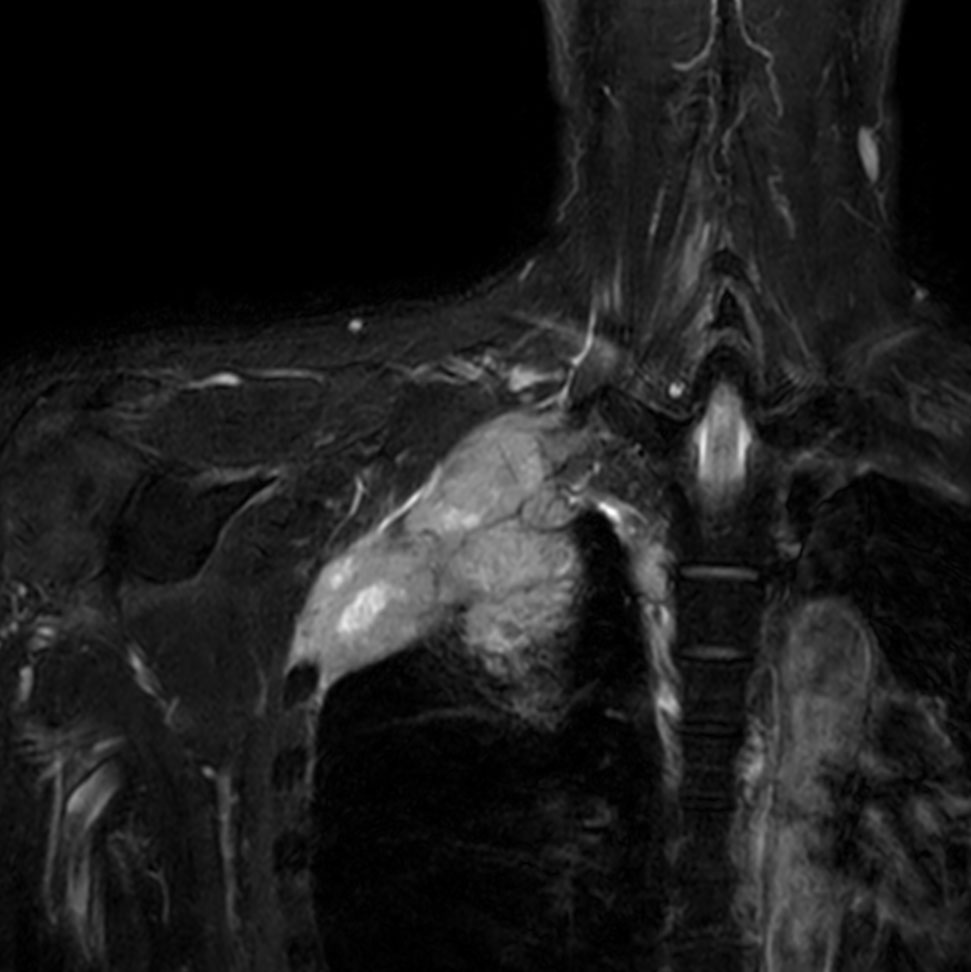

Coronal T2w TSE FatSat

Coronal 3D NerveVIEW (MIP)